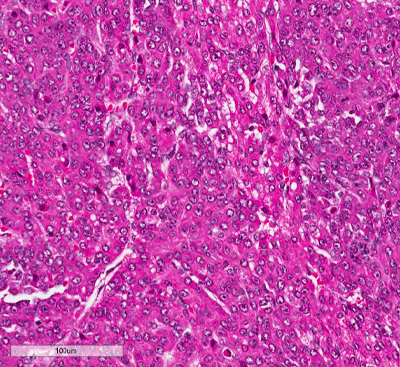

Figure 3. (Microscopic Photo, 20x) The fetal pattern of the tumor is composed of uniform cells resembling normal fetal hepatocytes. The cells are small with round centrally located nuclei, abundant clear to pink cytoplasm, and have distinct membranes.

Figure 4. (Microscopic Photo, 20x) The embryonal pattern consists of more primitive appearing cells in acini and sheets. These cells are small and angulated. The nuclei are larger than those of the fetal component nuclei and have coarse chromatin, scant cytoplasm, and indistinct membranes.